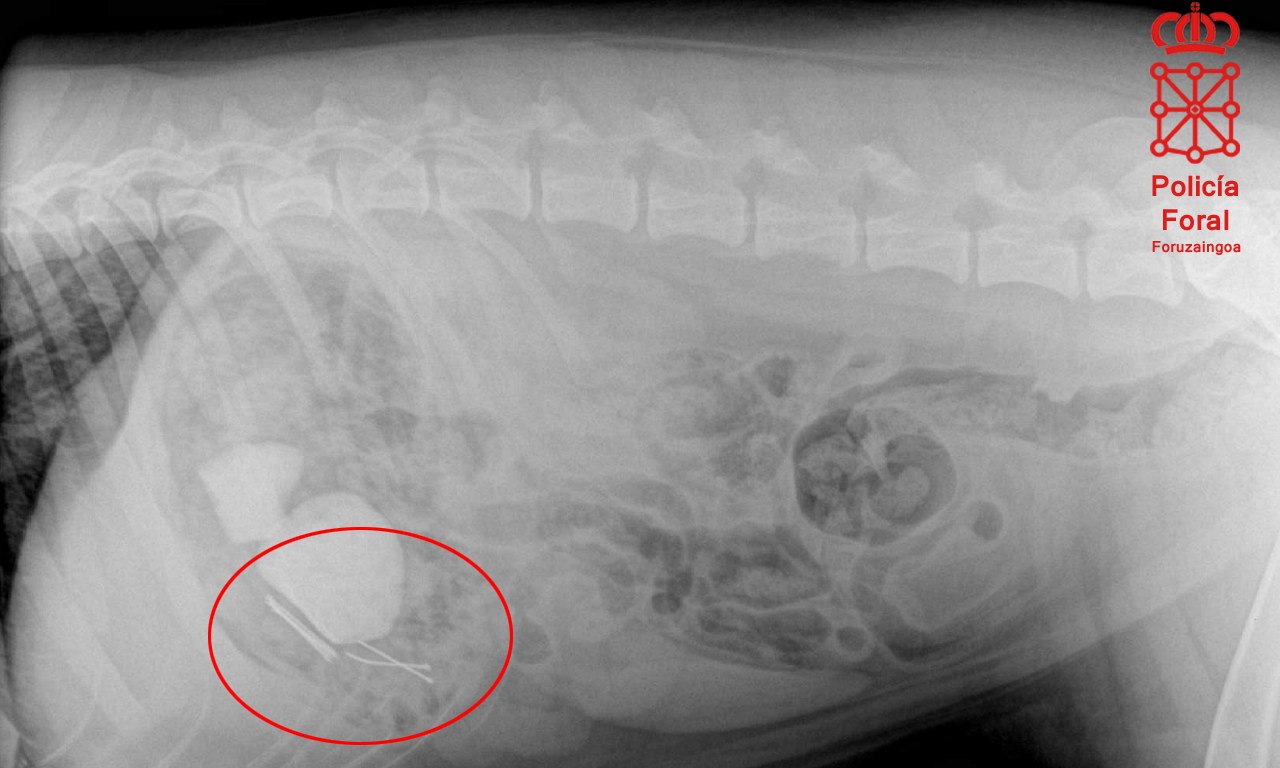

El animal fue trasladado inmediatamente a una clínica veterinaria, donde se le realizaron varias radiografías en las que se podían apreciar claramente varios clavos en el estómago, por lo que tuvo que someterse a una intervención quirúrgica para extraerlos e iniciar su recuperación.